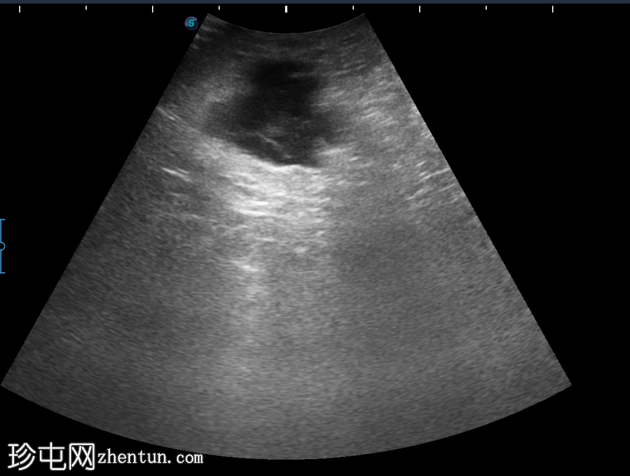

4-10点钟平面

浅表探头

在右前外侧肛周区域(具体位置为10-11点钟方向,紧邻肛壁)观察到一个边界清晰、大小约为5 x 5厘米的低回声病变。病变壁不规则,后部回声增强。病变内部回声提示可能存在肛周脓肿。

在此阶段,未见内部瘘管或与肛管的交通。此外,未检测到明显的病灶周围血管或气体灶。为了更好地评估病变的定位和范围,除了浅表探头外,可能还需要深层探头。